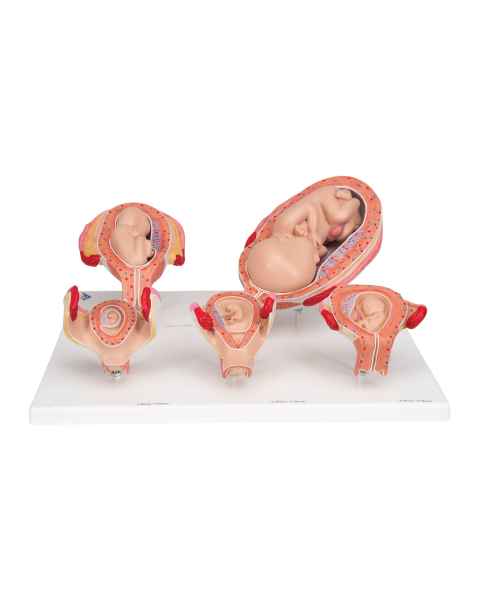

Female anatomical models are an ideal teaching aid to help educate both students and patients. Our extensive selection of female anatomy models includes female pelvic models, pregnancy series models, pelvis skeleton models, delivery/childbirth simulators, clinical breast trainers and self-exam models, uterus/ovary models, and more. Teaching simulators and self-exam models are excellent for educating students and patient education.

For example, the Wearable Breast Self-Exam Model can be easily worn, in order to better train and practice breast self-examination. Our line of prevention and detection models includes the Realistic Left Breast Model, Uterus/Ovary Model with Pathologies, Model of the Female Breast, and the Clinical Breast Trainer. Obstetricians will benefit from owning female anatomy figures of uteri and pelvises with fetuses inside, as well as sets of models that demonstrate the stages of fertilization. Women, particularly first-time mothers, will appreciate having a female education model that clearly illustrates the pregnancy process and what exactly is occurring inside of their body.